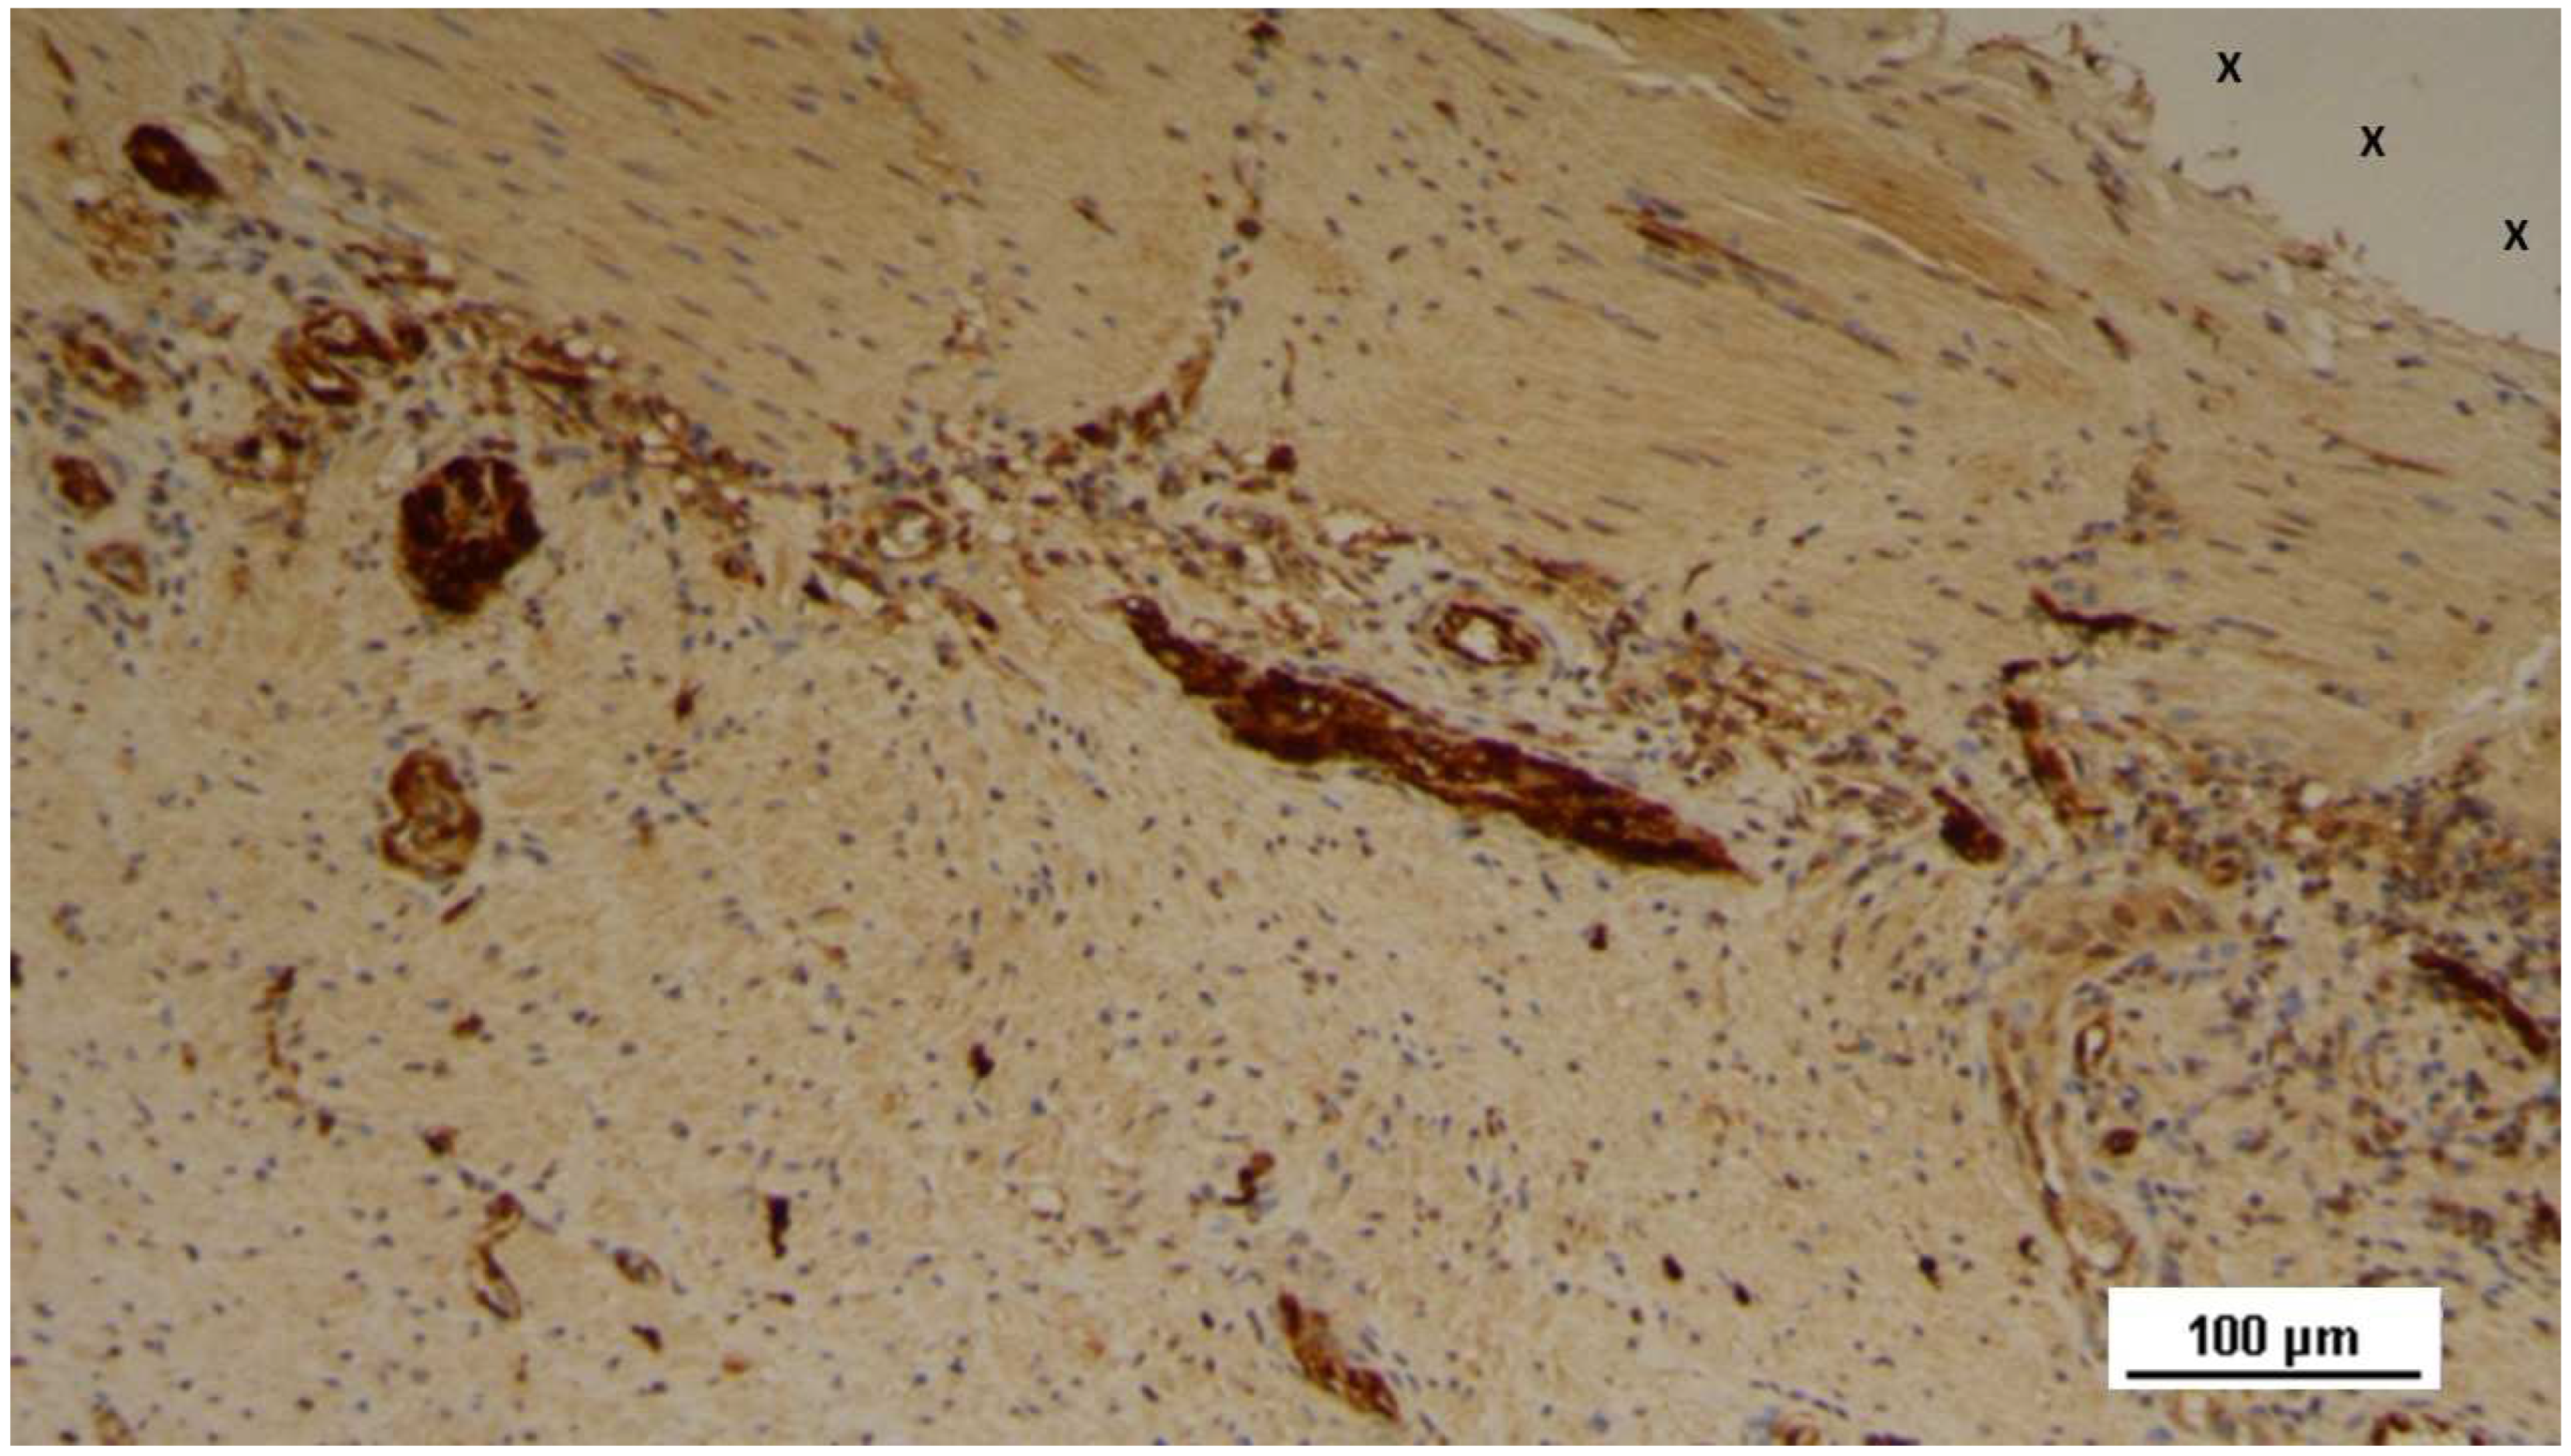

Figure 4. Biopsy specimen excised 4 weeks post-implantation (Short term - ST). VEGF-positive endothelial elements of early-stage vascular structures (white spots) are visible near the 3D scaffold of the S&S device (X). VEGF 100X).

The tissue specimens also exhibited clear evidence of vascular endothelial growth factor (VEGF)-mediated angiogenesis (Figure 4) and a marked CD31-positive response, which played a crucial role in vessel formation (Figure 5). Early formation of smooth muscle cells, as indicated by the presence of smooth muscle actin (SMA) positive elements, was also observed, though limited in extent (Figure 6)